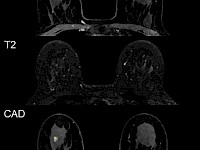

最新研究可減少MRI乳腺癌篩查中的假陽性

根據(jù)放射學雜志上的一項新研究,基于臨床特征和影像學發(fā)現(xiàn)的預(yù)測模型可能有助于降低接受 MRI 補充乳腺癌篩查的乳房致密女性的假陽性率?。